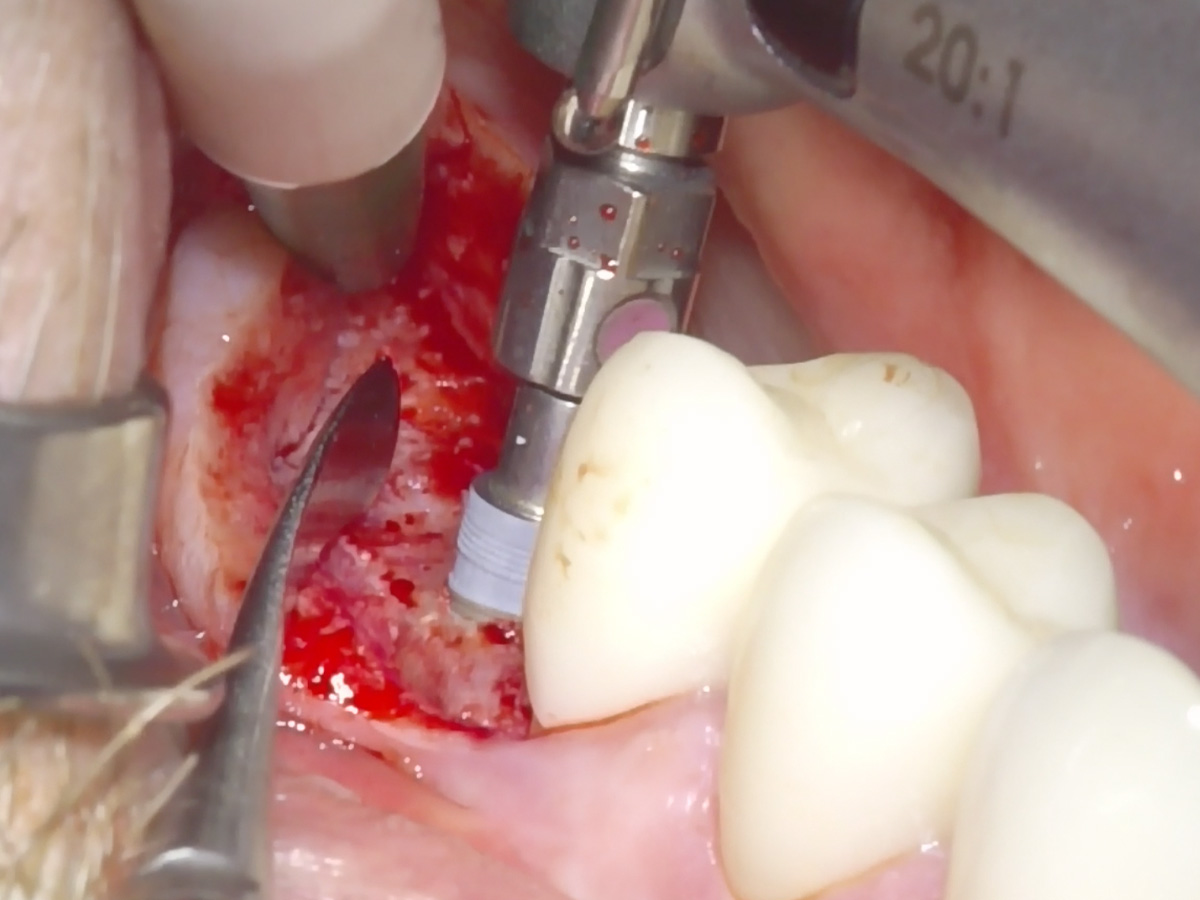

Abbildung 5

Implantatbettaufbereitung mit der Bone Condensing Methode (Versah Densah Burs).